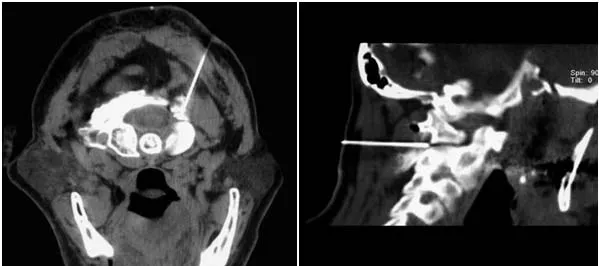

Найкраще проводити блокаду в місці проходження нерва поруч із міжхребцевим суглобом С1-2. Це дозволить не тільки заблокувати нерв, але й отримати лікувальний вплив на даний суглоб і навколосуглобові тканини. Виконати блокаду можна орієнтуючись на анатомічні структури, що визначаються шляхом промацування. Однак для збільшення ефективності процедури і зниження ризиків краще використовувати різні методи візуального контролю: ультразвук, цифрову рентгенівську флюороскопію або комп'ютерну томографію.

У клініці «Оберіг» можливе виконання даної блокади з використанням всіх перерахованих способів контролю. Найкращою є блокада під контролем МСКТ (мультизрізової спіральної комп'ютерної томографії). Використовуючи МСКТ, лікар підводить кінчик голки прямо до великого потиличного нерву, що значно підвищує ефективність процедури. При цьому чітко візуалізуються інші нервові і судинні утворення шиї (наприклад, хребетні артерії). Це дозволяє уникнути їх травмування і, таким чином, максимально знизити ризики для пацієнта.